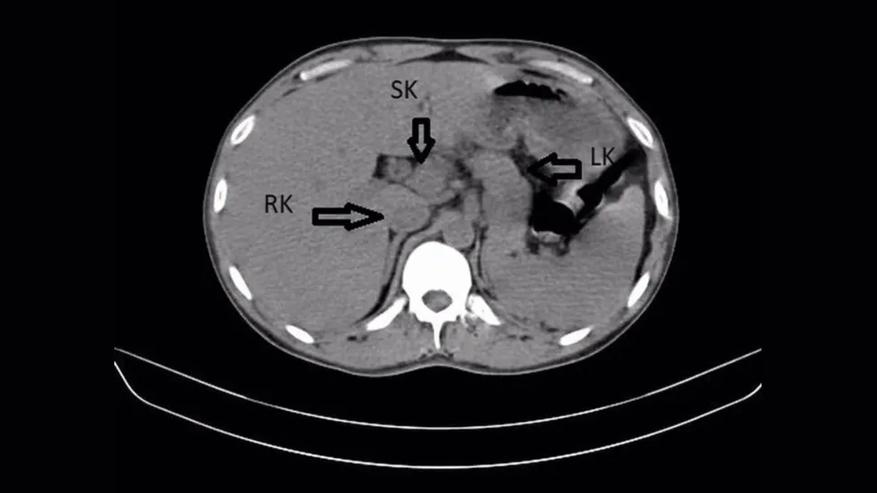

Анализы сразу подтвердили бактерию клебсиеллу пневмонии, которая вызвала воспаление. Чтобы разобраться до конца, специалисты провели компьютерную томографию. На снимках вместо двух почек оказалось три. Дополнительная почка плотно срослась с правой в форме подковы, и в ней тоже шло воспаление.